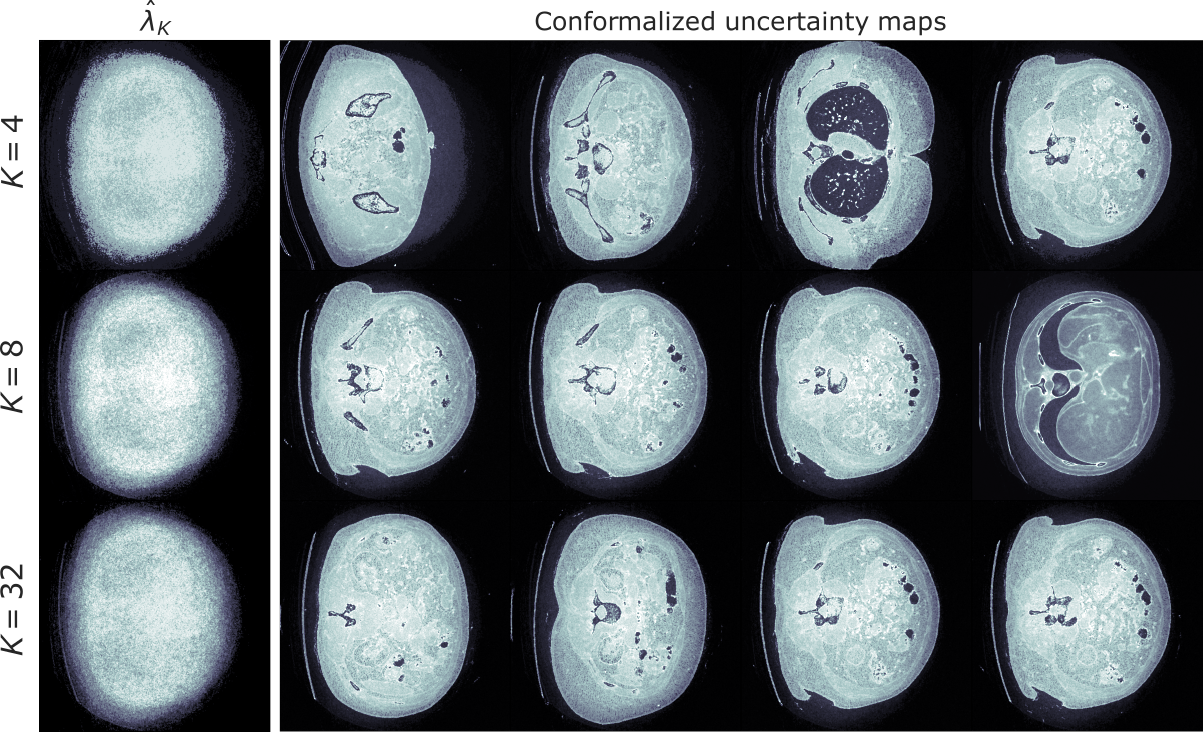

\(K\)-RCPS

For \(\bm{\lambda} \in \mathbb{R}^d\) define

\[\mathcal{I}_{\bm{\lambda}}(y)_j = [\text{lower} - \lambda_j, \text{upper} + \lambda_j]\]

and minimize the mean interval length with risk control

\[\hat{\bm{\lambda}} = \arg\min~\sum_{j \in [d]} \lambda_j~\quad\text{s.t. risk is controlled}\]

\[\bm{\lambda} = \arg\min~\sum_{j \in [d]} \lambda_j~\quad\text{s.t. risk is controlled}\]

For any user-defined membership \(M \in \mathbb{R}^{d \times K}\) :

1. Solve

\[\tilde{\bm{\lambda}}_K = \arg\min~\sum_{k \in [K]}n_k\lambda_k~\quad\text{s.t. convex upper bound} \leq \epsilon\]

2. Choose

\[\hat{\beta} = \inf\{\beta \in \mathbb{R}:~\text{risk is controlled},~\forall M\tilde{\bm{\lambda}}_K + \beta'\mathbb{1},~\beta' \geq \beta\}\]

\[\downarrow\]

\[\hat{\bm{\lambda}}_K = M\tilde{\bm{\lambda}}_K + \hat{\beta}\mathbb{1}\]

Mean interval length

\[\text{RCPS}~\quad~\text{ }~0.1614 \pm 0.0020\]

\[K\text{-RCPS}~\quad~0.1391 \pm 0.0025\]